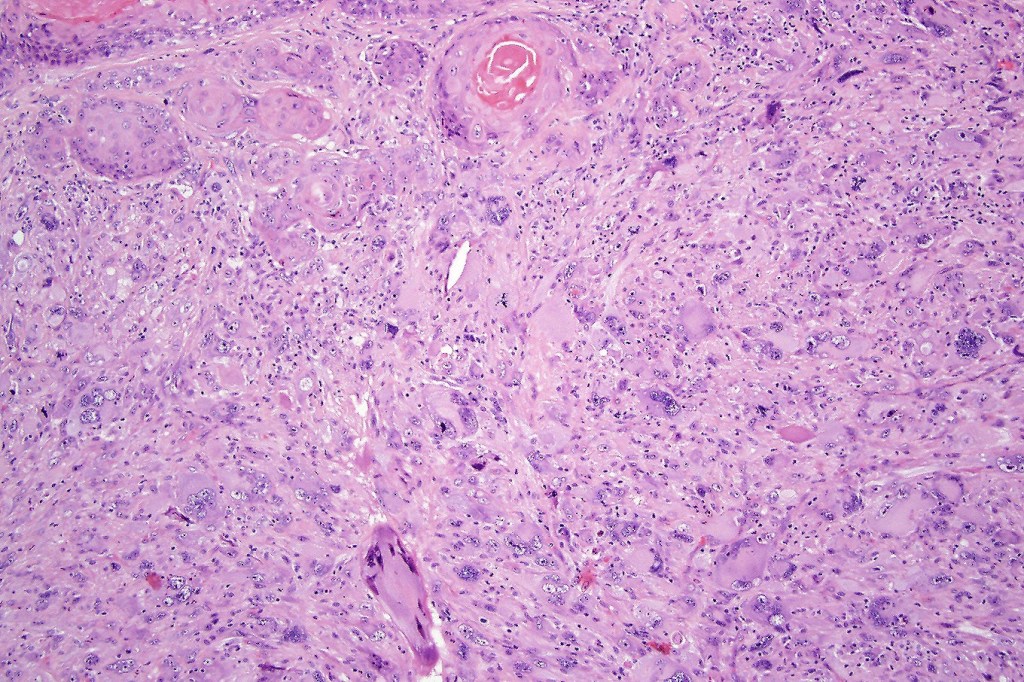

•Biphasic tumor

•Admixture of squamous carcinoma & pleomorphic spindled cell, osteoid, chondroid, MFH-like +/- osteoclast-like giant cells & rarely, smooth muscle, skeletal muscle, myofibroblastic or angiosarcomatous elements